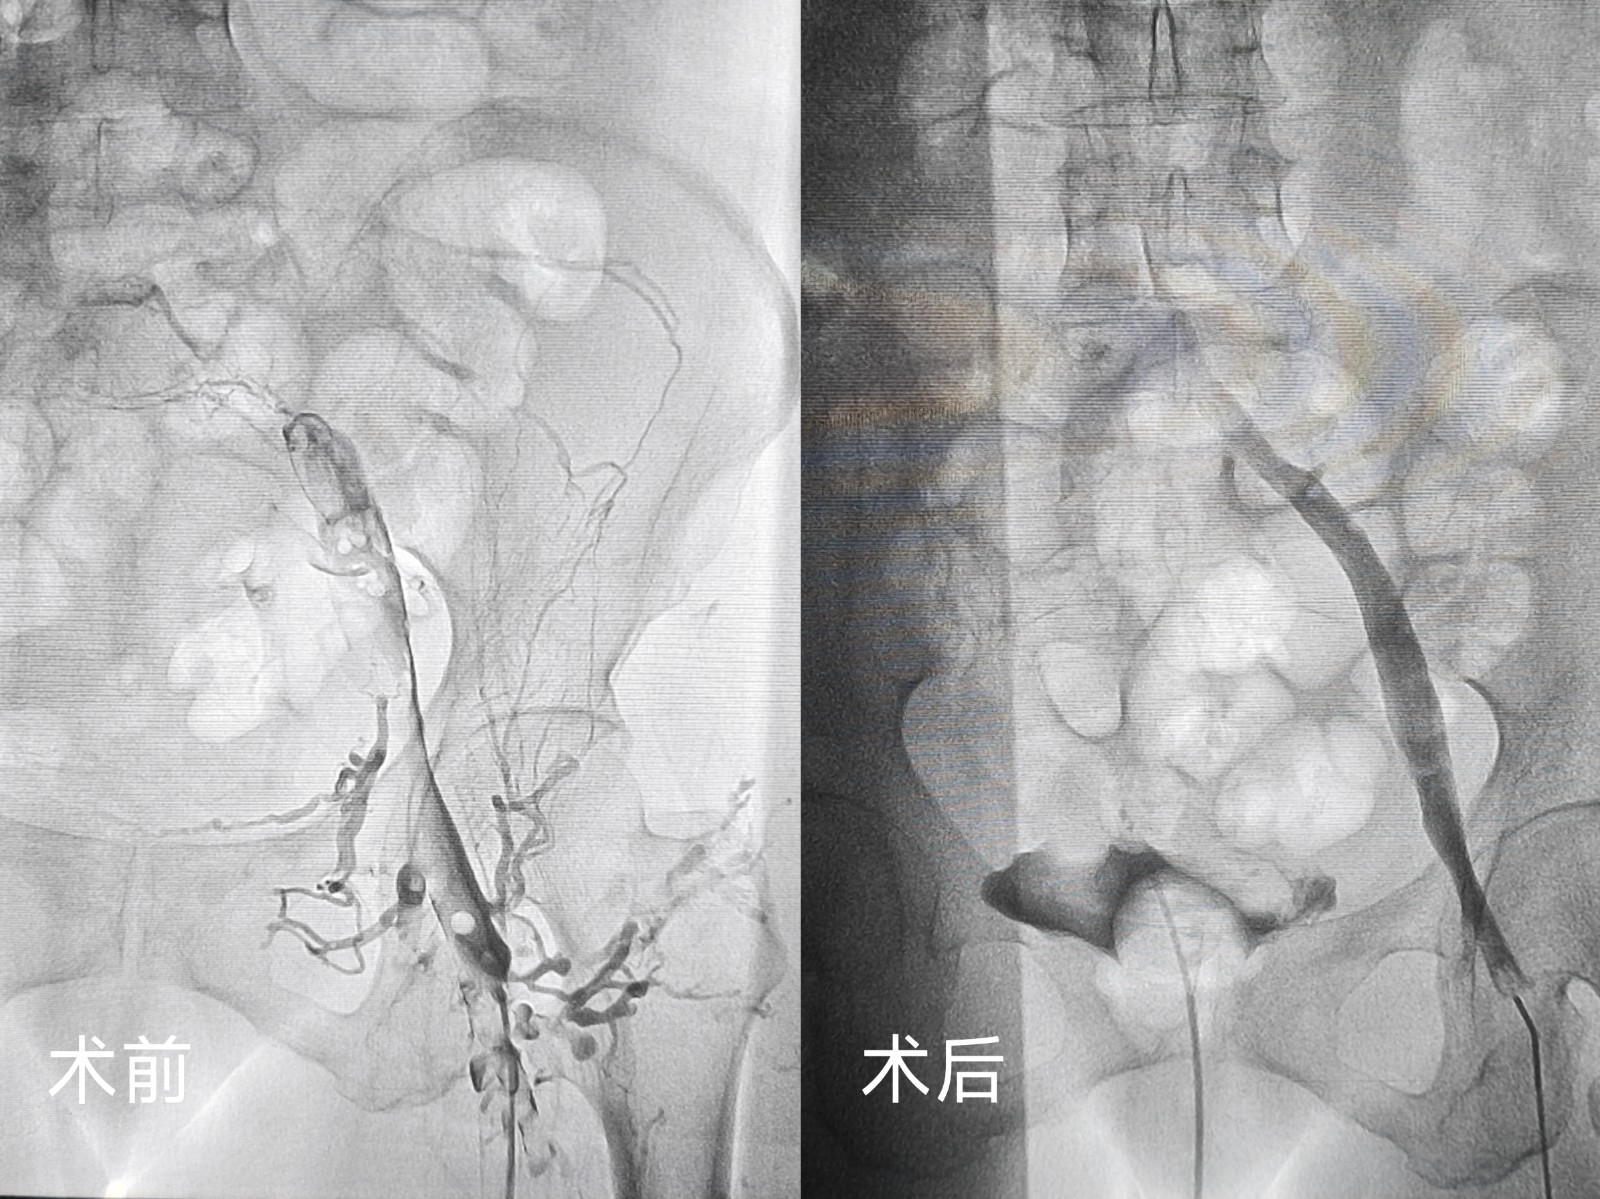

鄂西北首例应用患者因外伤导致双下肢深静脉血栓,转入十堰市人民医院心胸大血管外科时已在外院接受滤器置入术。患者外伤术后同时合并贫血,病情复杂且风险较高。传统的治疗方案失血量较高,科室医疗团队结合患者具体情况,制定了个性化治疗方案,决定采用外周静脉取栓支架系统实施下腔静脉及下肢静脉取栓术。手术过程中,团队发现此前置入的滤器内已形成血栓,为避免血栓脱落风险,当即调整手术方案,在精准置入新滤器后,成功回收旧滤器,同时利用外周静脉取栓支架系统高效清除静脉内阻塞血栓。

无独有偶,一位左下肢突发肿胀伴剧烈疼痛的患者,在症状出现仅1天后便慕名前来求医。患者病情进展迅速,肢体肿胀明显,疼痛难忍,严重影响正常行走。科室团队快速响应,经详细检查后明确诊断为左下肢深静脉血栓,随即为患者安排紧急手术。术中,团队先为患者置入滤器预防肺栓塞,再运用同款外周静脉取栓支架系统,精准、高效地清除了下肢静脉内的血栓。